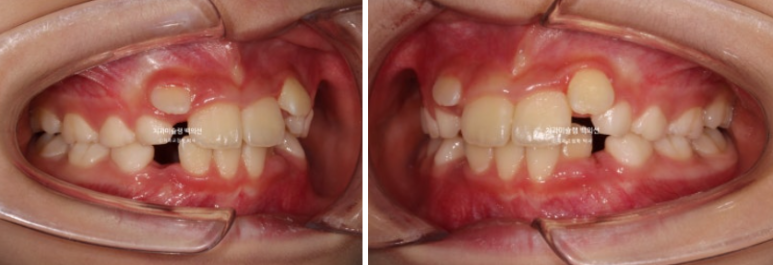

골격분석상 하악골 여성장을 동반한 무턱으로 진단되어 치료 목표는

-

악궁확장을 통한 덧니 해소

MA 기능으로 하악성장 유도

이 두가지가 되겠습니다.

손 엑스레이 성장판 분석한 결과 최대 성장기가 시작되는 시점이라 타이밍도 아주 좋습니다.

인비절라인 퍼스트로 권유드렸고 치료를 시작했습니다.

치료계획은 전반부의 악궁확장 및 덧니해소 단계와 후반부의 MA를 통한 하악성장 유도 두단계로 나뉩니다.